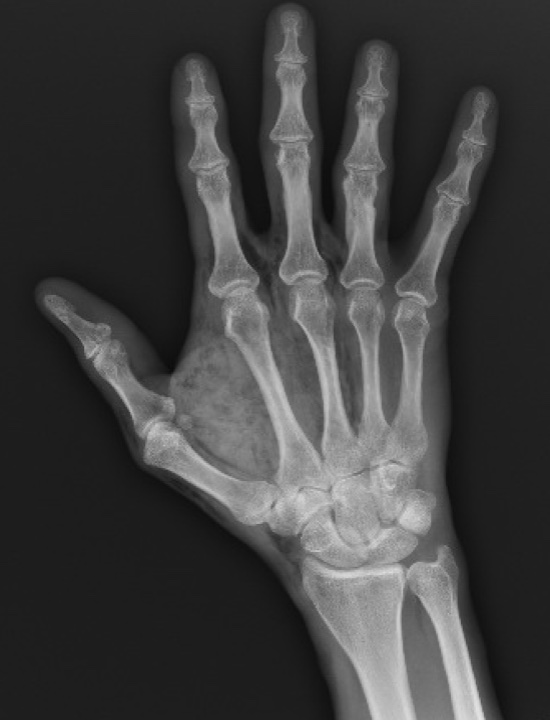

What’s the diagnosis? Gepost op 30 september 202024 september 2020 door netwerkvsseh What’s the diagnosis? By Dr. Jacob Martin @emdaily.cooperhealth.org Dit delen: Delen op X (Opent in een nieuw venster) X Share op Facebook (Opent in een nieuw venster) Facebook Delen op LinkedIn (Opent in een nieuw venster) LinkedIn E-mail een link naar een vriend (Opent in een nieuw venster) E-mail Afdrukken (Opent in een nieuw venster) Print Vind-ik-leuk Aan het laden... Gerelateerd